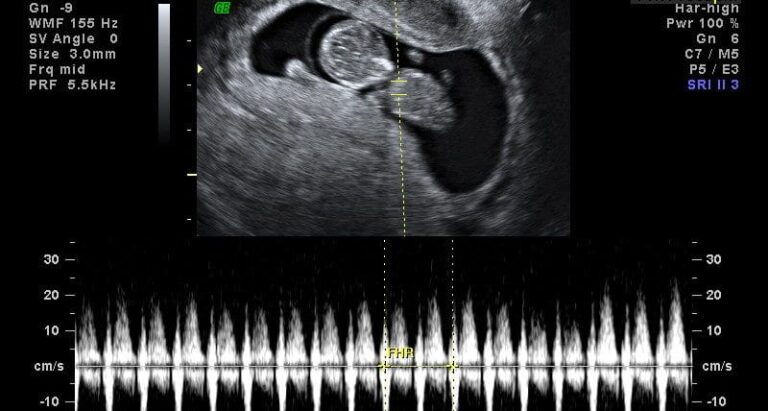

Qual é a frequência cardíaca normal do feto?

Esta é uma pergunta que você provavelmente tem desde a primeira vez que você ouviu bater o seu…